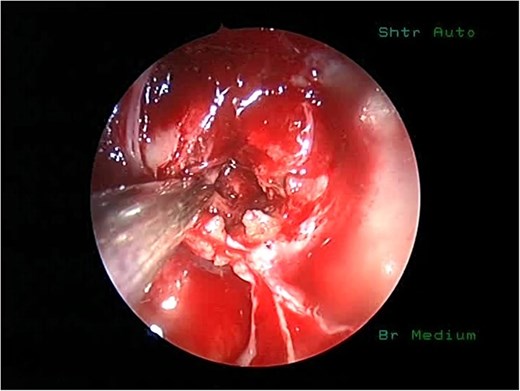

She underwent endoscopic trans-sphenoidal debulking of the suprasellar lesion (Figs 3 and 4). Postoperatively, the patient developed complications, including diabetes insipidus and panhypopituitarism, requiring levothyroxine and corticosteroid replacement therapy. Histopathology revealed a diagnosis of high-grade primary central nervous system (CNS) B-cell lymphoma. Microscopic analysis showed sheets of atypical lymphoid cells with high mitotic activity. Consequently, the patient was initiated on rituximab and high-dose methotrexate (HD-MTX). Nevertheless, methotrexate was terminated due to the onset of acute kidney injury. Given the patient's intolerance to further HD-MTX, nivolumab was commenced based on PD-L1 expression. While there was partial symptom relief, the tumor response was inadequate. Therefore, the patient underwent whole-brain radiotherapy with a boost to the pituitary region, receiving a total dose of 45 Gy over 25 fractions. This treatment was effective, though she experienced alopecia, mild nausea, blurred vision, headaches, and severe vulvar itching.